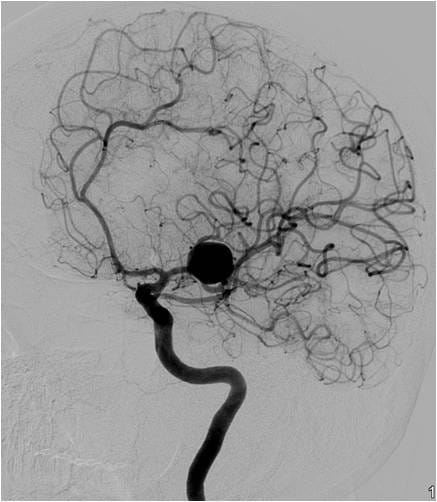

This video documents the surgical clipping of a giant middle cerebral artery aneurysm. The patient is a 56-year-old woman with a Grade I subarachnoid hemorrhage.

Supplemental photos also accompany the video below.